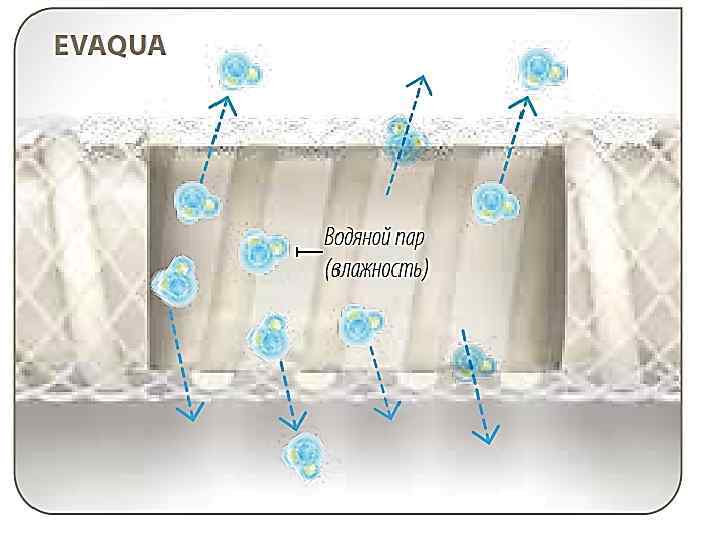

Контаминации нет! Нет контаминации!

Контаминации нет! Нет контаминации!

Колонизации микробами нет! Вода в камере увлажнителя остается стерильной При соблюдении: стерильная вода одноразовые камеры увлажнителей 5 дней-замена контура

Колонизации микробами нет! Вода в камере увлажнителя остается стерильной При соблюдении: стерильная вода одноразовые камеры увлажнителей 5 дней-замена контура